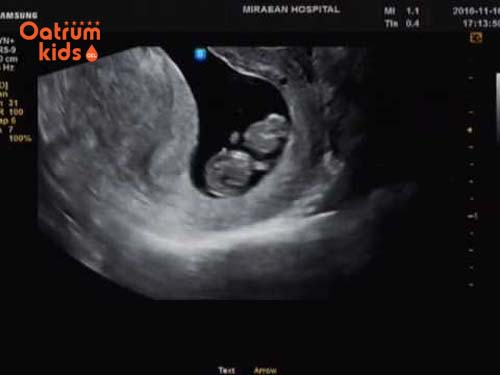

Lúc này khi đi siêu âm là mẹ có thể nghe được nhịp tim thai đập thông qua ống nghe Doppler, nhịp tim con dao động 110-160 nhịp/phút.